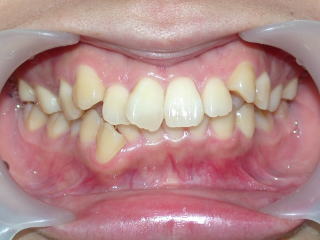

2022年7月25日初診、20代女性の叢生症例 (新潟県長岡市要町 要町歯科 歯科矯正 歯列矯正)

前歯のデコボコが気になる、とのことです。

2022年7月→2024年5月(2年弱でした。これから保定期間に入ります。)